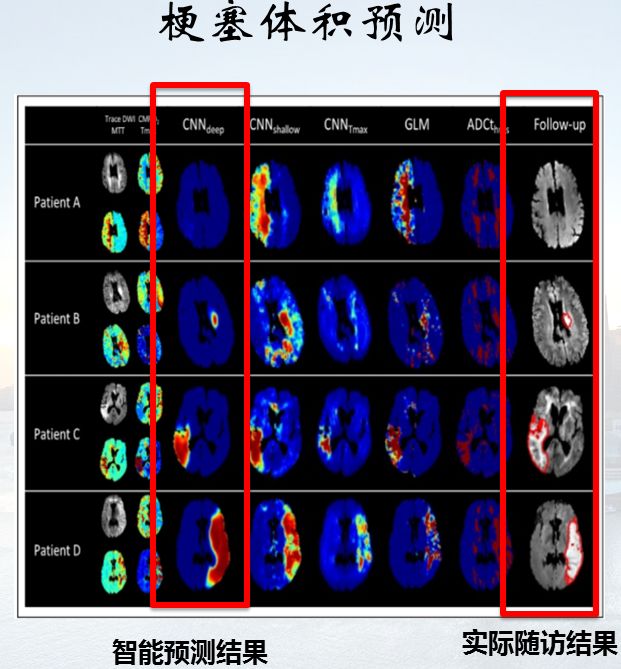

2018年neuroradiology杂志发表文章显示基于ct的自动化aspect评分系统